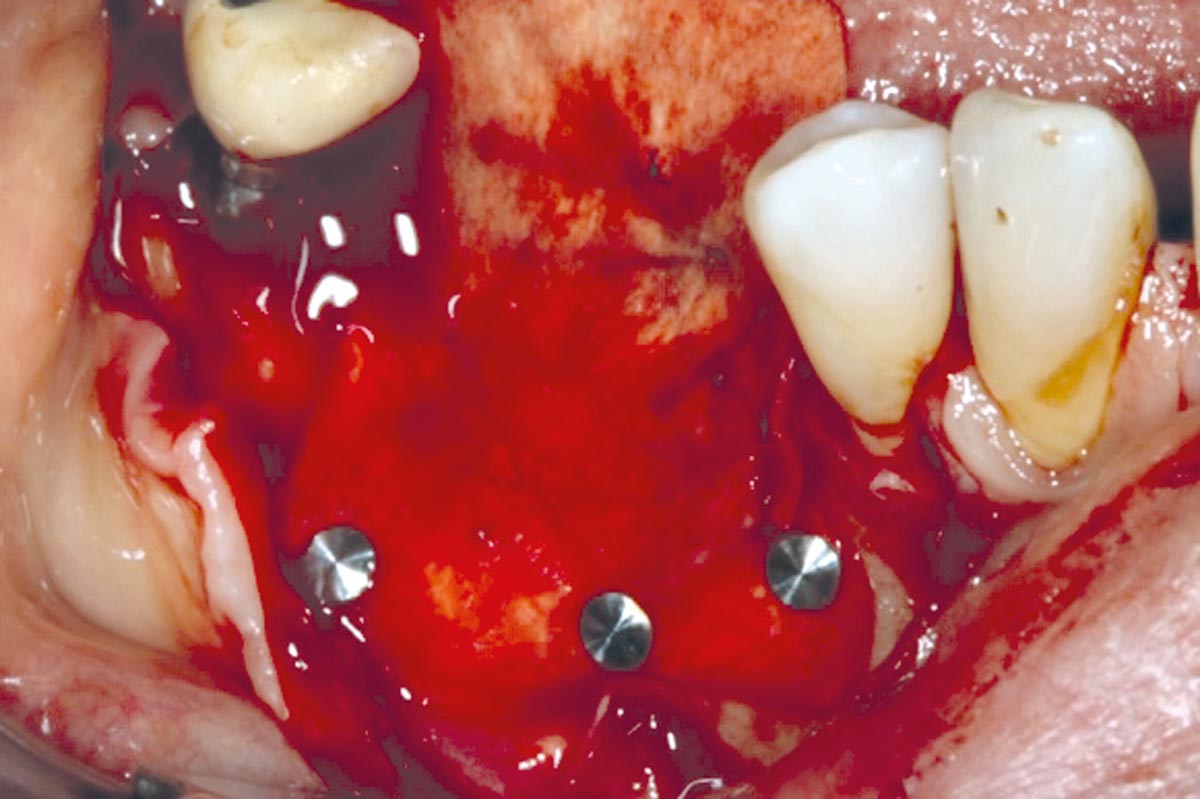

4/10 - Jason membrane® fliped buccally.GBR with cerabone® and Jason® membrane DentalPro - Dr. A. Gargiulo

5/10 - cerabone® mixed with autologous bone.GBR with cerabone® and Jason® membrane DentalPro - Dr. A. Gargiulo

8/10 - Re-entry at 4 months.GBR with cerabone® and Jason® membrane DentalPro - Dr. A. Gargiulo